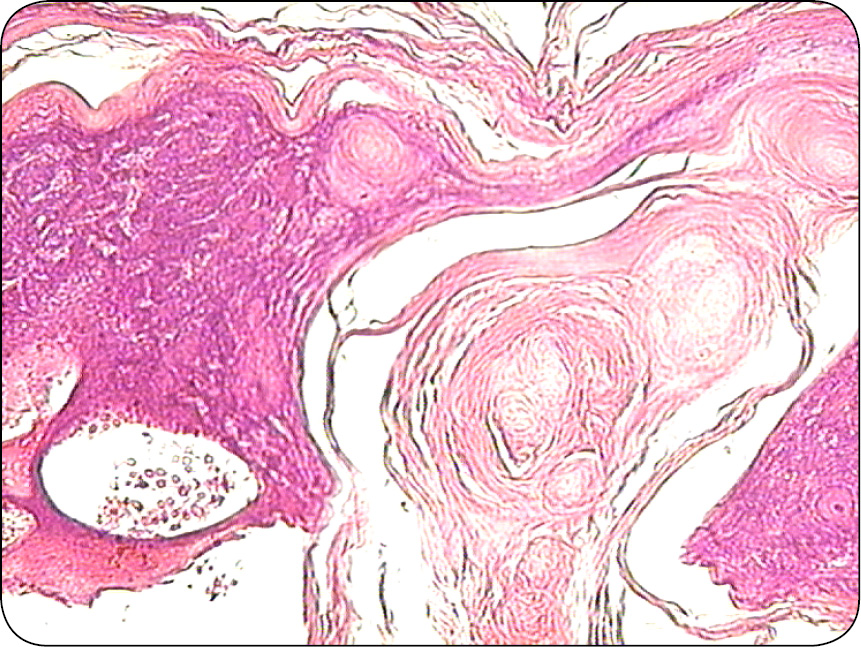

Jest guzem wywodzącym się z komórek macierzy włosa. Zbudowany z licznych torbieli, których zawartość ulega inkrustacji solami wapnia. Ściana torbieli jest zbudowana z kilku warstw komórek, które ulegają zwyrodnieniu i nekrobiozie, wypełniają światło torbieli (ryc. 9). W świetle torbieli znajduje się homogenna eozynochłonna masa, w której są widoczne cienie komórkowe (ryc. 10). Stąd wywodzi się angielskie określenie „cieni komórkowych” – shadow cells. Cechą charakterystyczną tych guzów jest wapnienie obumarłych komórek obecnych w świetle torbieli (ryc. 11).